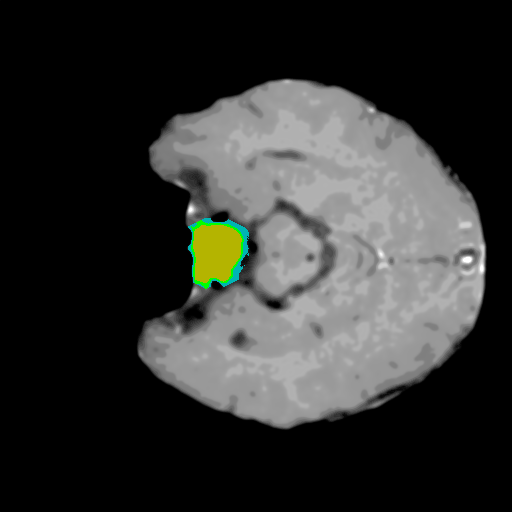

Extensive experiments have been performed in the current setup, and experimental outcomes are reported with the demonstration of numerical and statistical analyses using the proposed QFS-Net, QIS-Net [39], convolutional U-Net [18] and Residual U-Net (URes-Net) architectures [20]. The human expert segmented skull-tripped contrast enhanced DSC brain MR input image slices of size and ROIs are provided in Figure 5 as samples. The demonstration of QFS-Net segmented images followed by the essential post-processed outcome on the slice no. for class level with four distinct activation schemes () are shown in Figure 6. It is evident from the experimental data provided in Table LABEL:tab1 that the proposed QFS-Net performs optimally for the -connected quantum fuzzy pixel information heterogeneity assisted activation () with and gray scale set in comparison with other thresholding schemes and gray scale sets under the four evaluation parameters () [44]. The segmented tumors obtained using the proposed self-supervised procedure under class transition levels with four different thresholding schemes , , and are demonstrated in Figures 7- 8 for the class boundary sets and [39], respectively. The segmented images using the remaining two class boundary sets ( and ) [39] are provided in the supplementary materials section. The segmented ROIs describing the whole tumor region after the masking procedure using QIS-Net, U-Net and URes-Net are also reported in Figure 9.